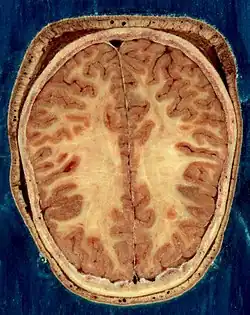

Головной мозг взрослого человека в разрезе